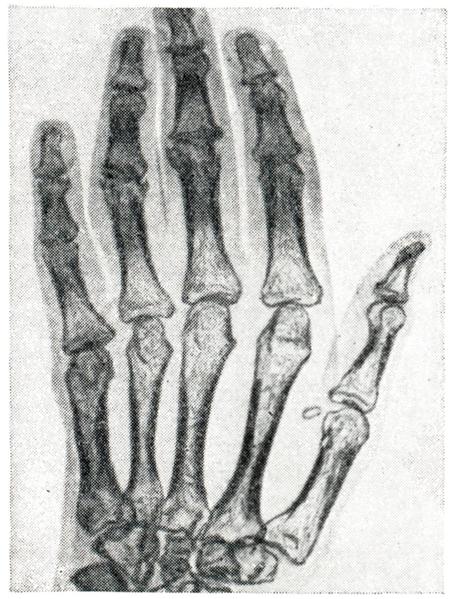

Рентгенологическая симптоматика артрита многообразна и включает следующие признаки: остеопороз во всех его разновидностях; иногда расширение суставной щели или чаще ее сужение (тотальное или частичное) в связи с наличием деструктивных изменений в костно-хрящевых элементах сустава; краевые костные дефекты, так наз. узуры, на суставных поверхностях как следствие деструктивных процессов; наличие очагов деструкции в околосуставных участках костей; образование секвестров, нередко наблюдаемое при специфических, в частности туберкулезных, артритов (рис. 8); периостальные наложения в области метафизов длинных трубчатых костей, а также реактивный остеосклероз; изменения рельефа суставных поверхностей костей и краевые костные разрастания на костях, образующих сустав; вывихи и подвывихи, возникающие в результате деформации суставов при некоторых формах артрита (рис. 9).

Рис. 9.

Кисть и луче-запястный сустав женщины, страдающей ревматоидным артритом более 20 лет. Резкая деформация суставов с наличием патологических вывихов и подвывихов. Мощные костные разрастания на краях эпифизов пястно-фаланговых суставов (рентгенограмма).